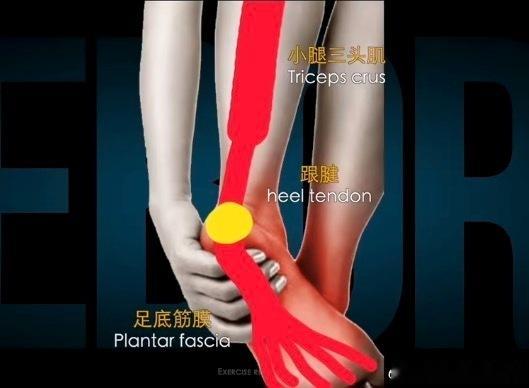

【足底筋膜炎原因】①小腿三头肌和跟腱的过度使用——我们小腿三头肌移形成跟腱,跟腱跨过跟骨和足底筋膜是移形存在的,所以张力也是共通的。

很多朋友喜欢踮着脚走路,或运动时用小腿去发力,那如果小腿过度紧张,足底筋膜的张力也会很高,导致疼痛。

✅解决办法:这种情况下,小腿三头肌的放松以及牵拉,能缓解足底筋膜的疼痛。